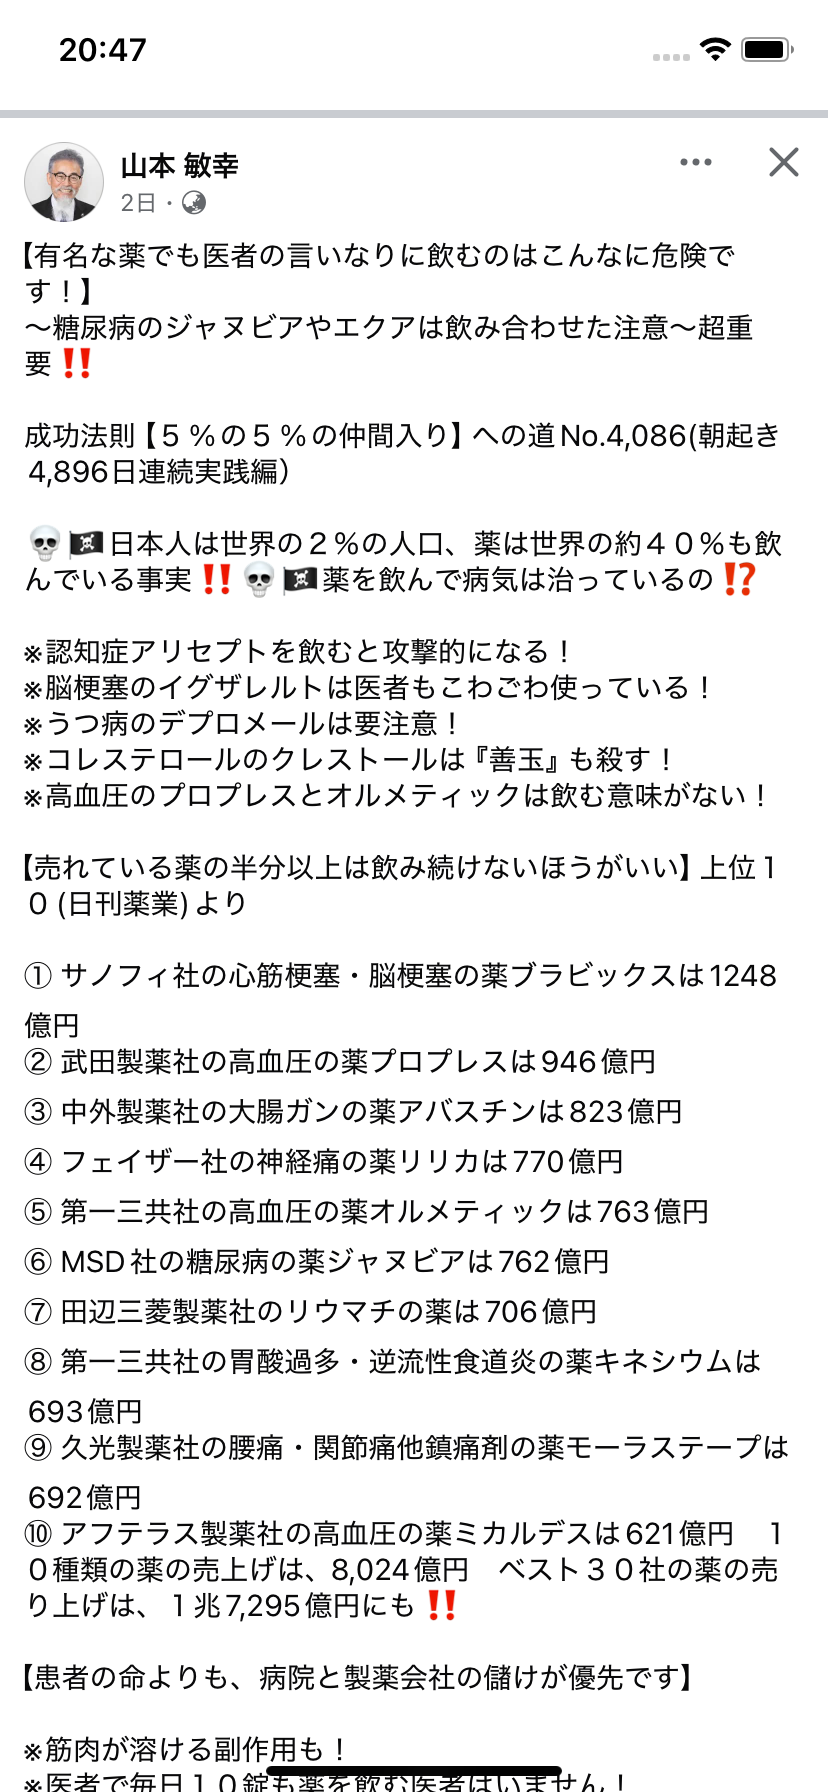

有名な薬でも医者の言いなりに飲むのはこんなに危険です! 出典・フェイスブック

iPhoneから送信

2025.01.25